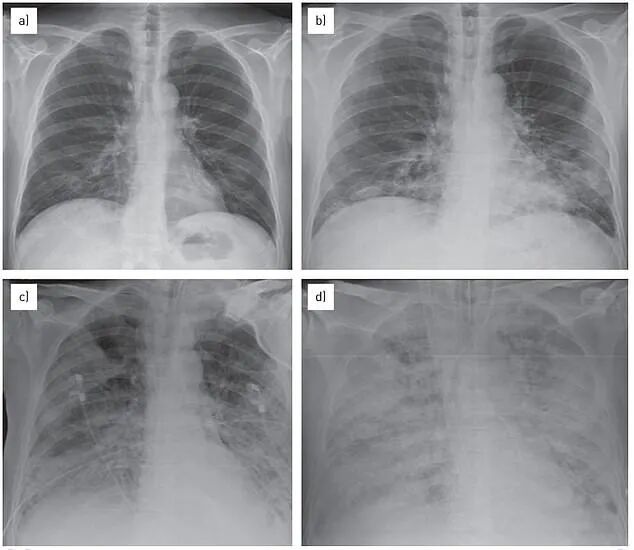

多重感染导致白肺

科恩周四上午在国会作证时表示,截至目前并不认为是一种新的病原体,相信现在出现的“白肺病例”是由于新冠病毒、流感、呼吸道合胞病毒、支原体等多重感染导致的症状。